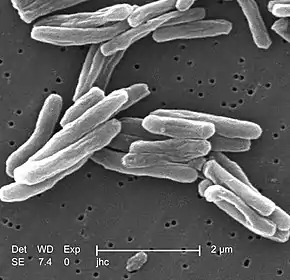

Cord factor, or trehalose dimycolate (TDM), is a glycolipid molecule found in the cell wall of Mycobacterium tuberculosis and similar species. It is the primary lipid found on the exterior of M. tuberculosis cells.[1] Cord factor influences the arrangement of M. tuberculosis cells into long and slender formations, giving its name.[2] Cord factor is virulent towards mammalian cells and critical for survival of M. tuberculosis in hosts, but not outside of hosts.[3][4] Cord factor has been observed to influence immune responses, induce the formation of granulomas, and inhibit tumor growth.[5] The antimycobacterial drug SQ109 is thought to inhibit TDM production levels and in this way disrupts its cell wall assembly.[6]

A cord factor molecule is composed of a sugar molecule, trehalose (a disaccharide), composed of two glucose molecules linked together. Trehalose is esterified to two mycolic acid residues.[7][8] One of the two mycolic acid residues is attached to the sixth carbon of one glucose, while the other mycolic acid residue is attached to the sixth carbon of the other glucose.[7] Therefore, cord factor is also named trehalose-6,6'-dimycolate.[7] The carbon chain of the mycolic acid residues vary in length depending on the species of bacteria it is found in, but the general range is 20 to 80 carbon atoms.[3] Cord factor's amphiphilic nature leads to varying structures when many cord factor molecules are in close proximity.[3] On a hydrophobic surface, they spontaneously form a crystalline monolayer.[9] This crystalline monolayer is extremely durable and firm; it is stronger than any other amphiphile found in biology.[10] This monolayer also forms in oil-water, plastic-water, and air-water surfaces.[1] In an aqueous environment free of hydrophobic surfaces, cord factor forms a micelle.[11] Furthermore, cord factor interlocks with lipoarabinomannan (LAM), which is found on the surface of M. tuberculosis cells as well, to form an asymmetrical bilayer.[1][12] These properties cause bacteria that produce cord factor to grow into long, intertwining filaments, giving them a rope- or cord-like appearance when stained and viewed through a microscope (hence the name).[13]